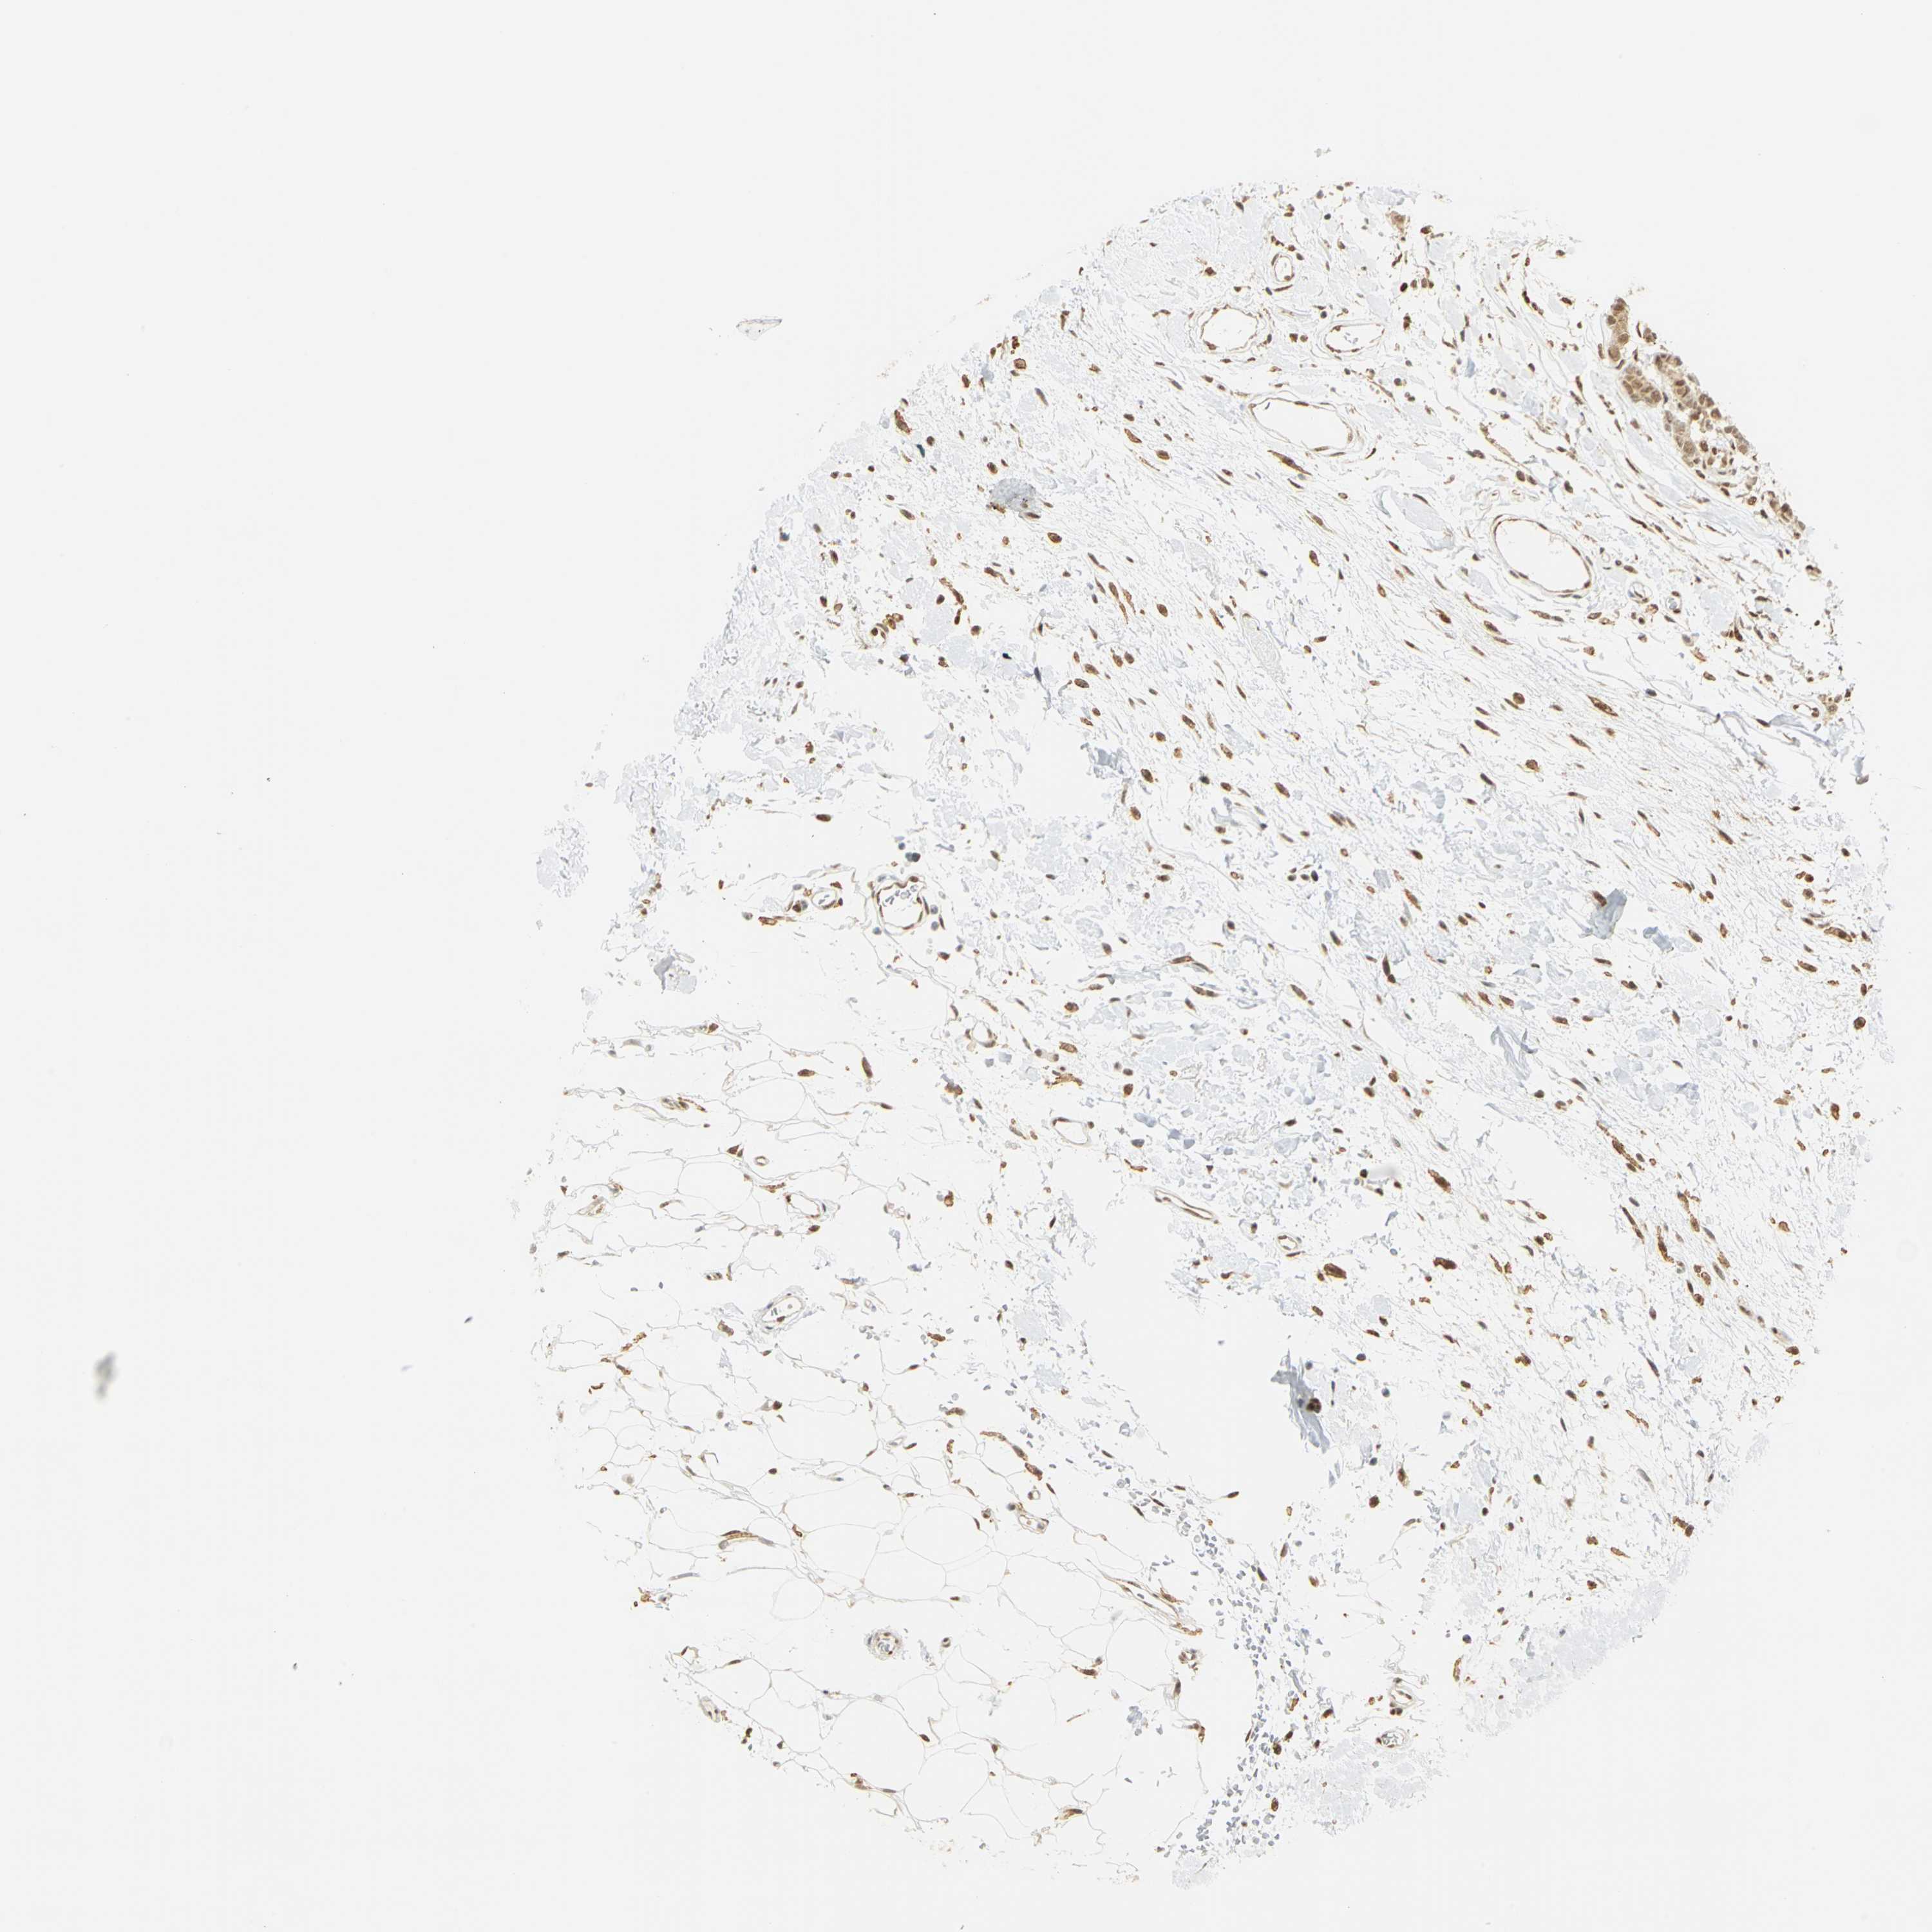

CANCER BREAST CANCER Show tissue menu

BRCA TCGA BRCA VALIDATION PROTEIN EXPRESSION